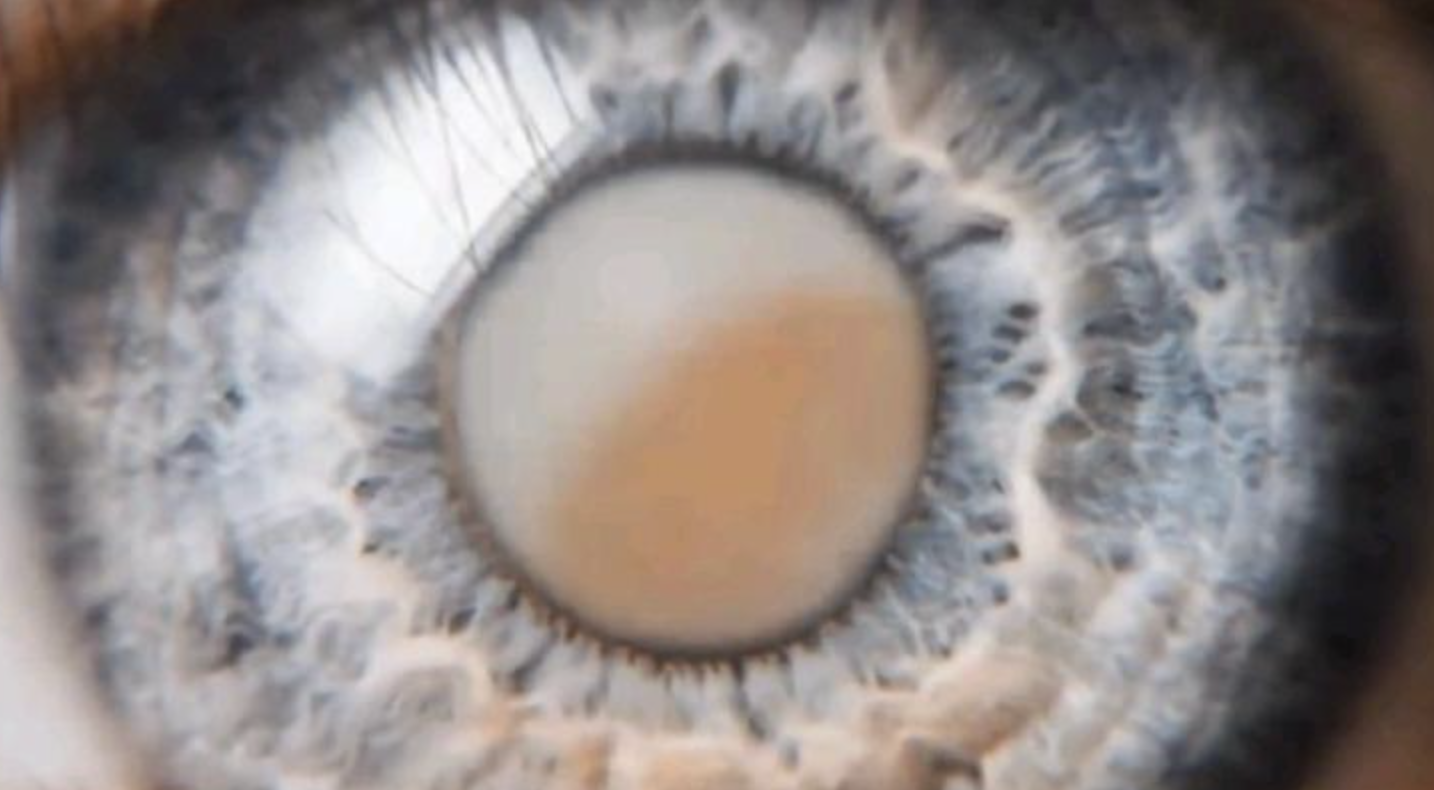

세계 1위 유튜버 미스터 비스트! 시각장애인의 시력을 찾아주다

이런것이 진짜 선한 영향력이 아닐까요?